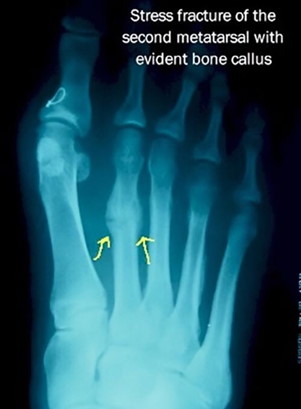

To get a better understanding of what is happening inside your foot, imaging tests may be necessary.

An MRI scan can detect a stress fracture in its early stages, even before an X-ray, however X-rays will often be taken first.

MRI scans are more sensitive than x-rays, which can only detect stress fractures after the healing process has begun.